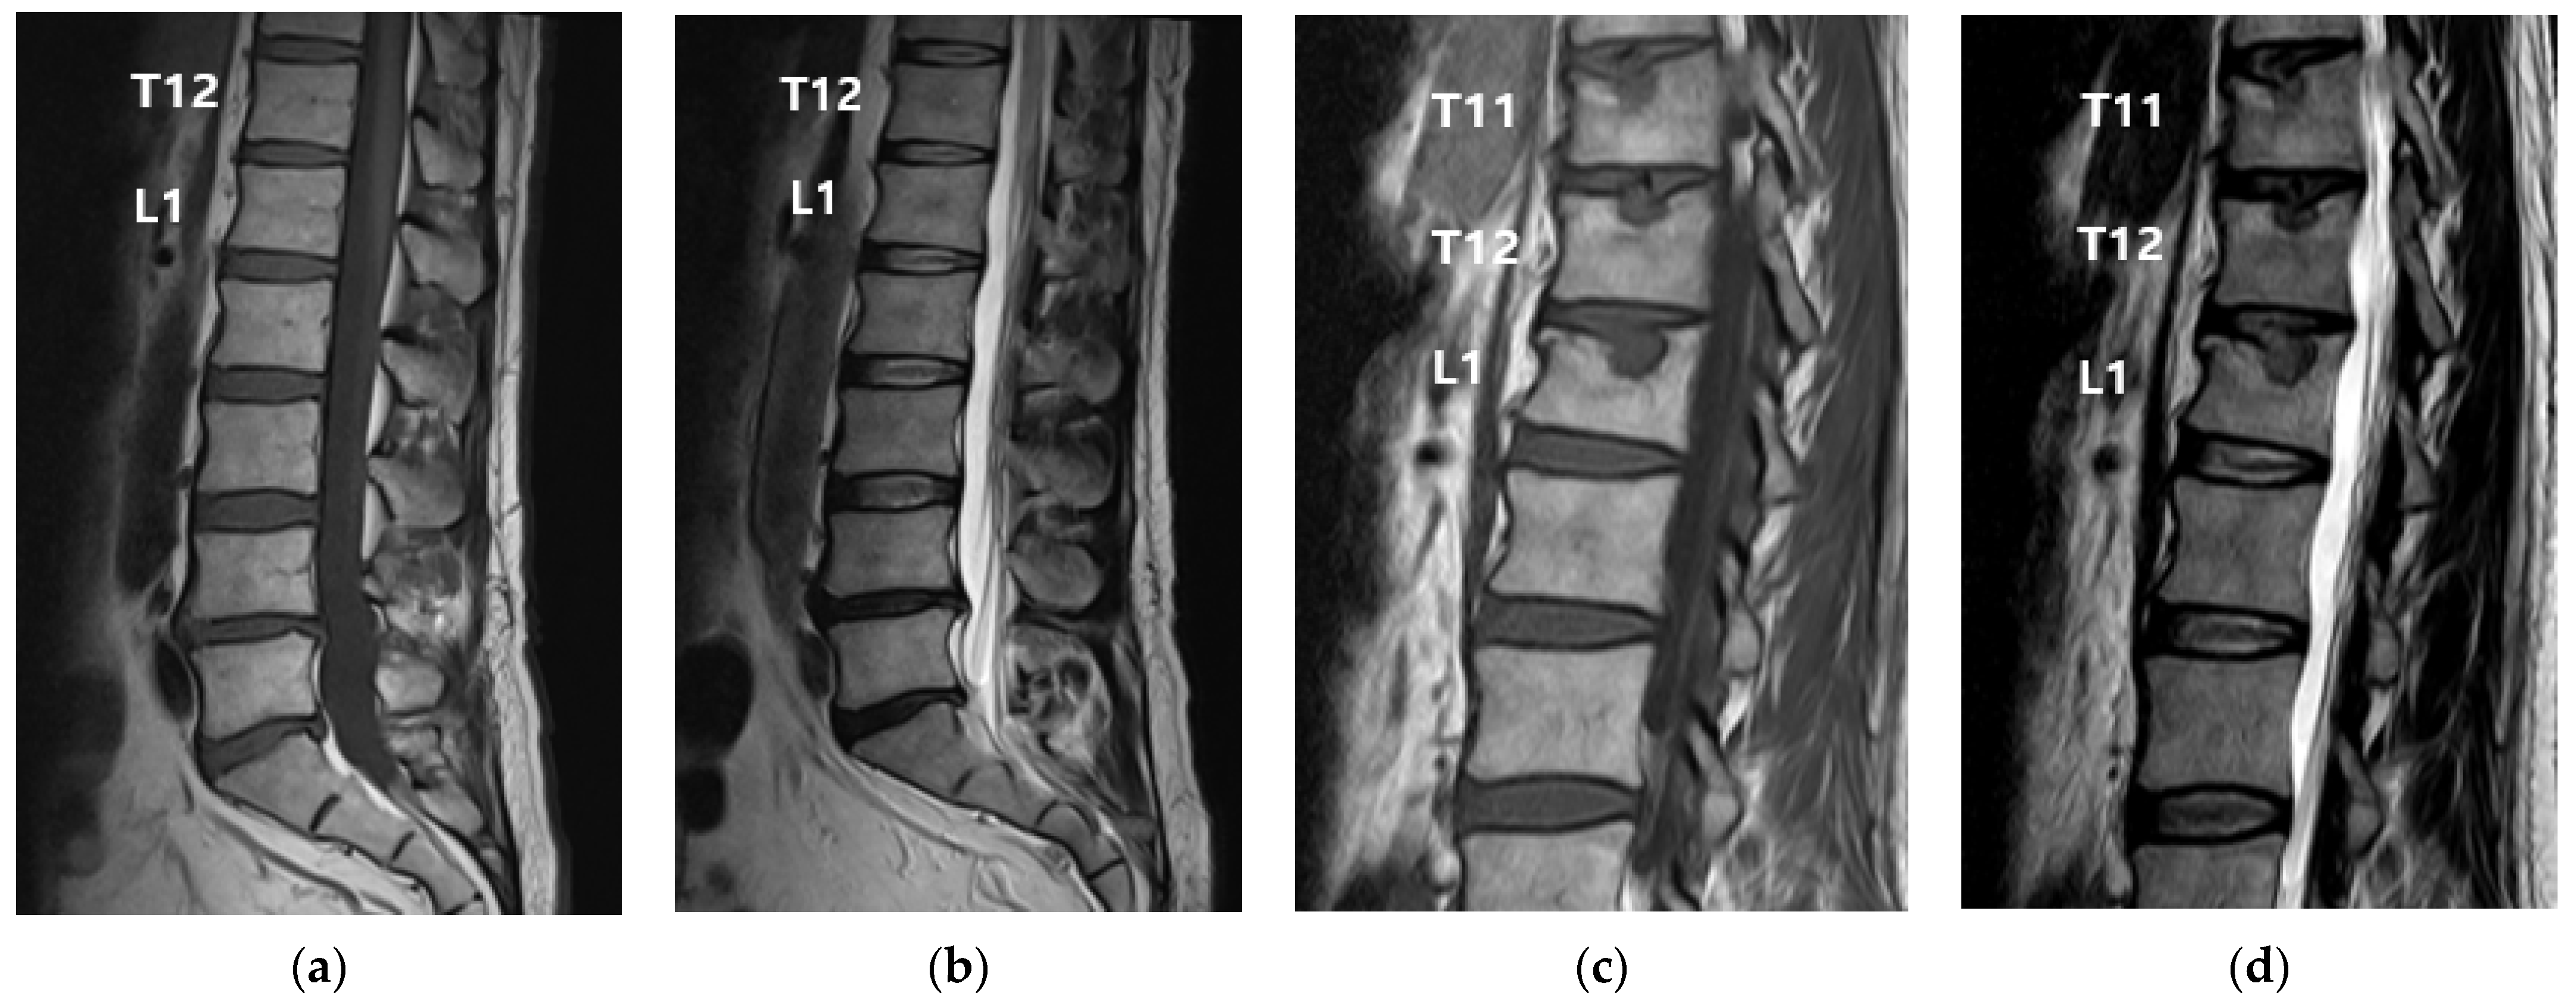

2. Case Presentation